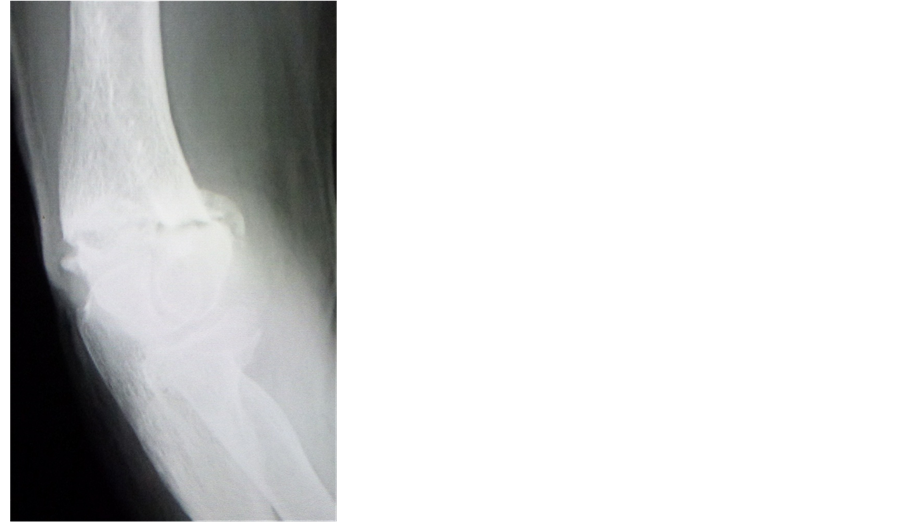

An 87-year-old woman was injured by a fall. She consulted a local doctor and was diagnosed with a distal humerus fracture, for which she underwent plaster cast fixation treatment. However, she was introduced to our hospital because bone union had not occurred, even after three months of therapy. On plain radiographs or computed tomography (CT) images, there was no transposition of the fractured bone, but instead, a bone fracture gap was seen (Figure 1). The border of the fractured bone was stiffened; however, a callus formation was no confirmed. There was not clinical or laboratory evidence of infection. Therefore, we made the diagnosis of nonunion.

Figure 1. Plain radiographs (a) and (b) showed the nonunion of the distal humerus fracture at the first visit to our hospital.